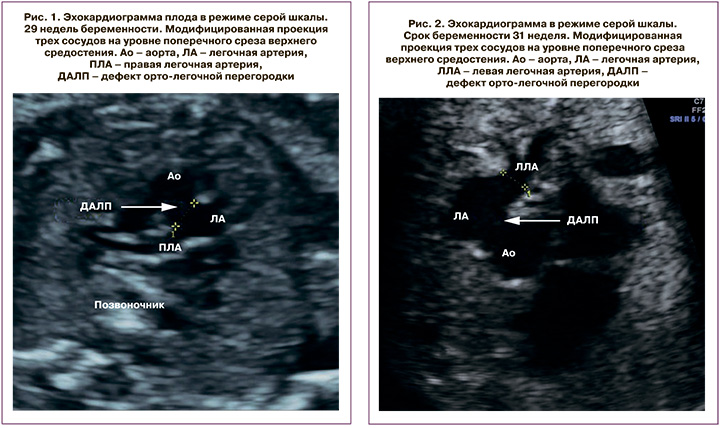

Семейный анамнез пациентки не был отягощен. Толщина воротникового пространства в I триместре составила 1,6 мм. Анатомическое исследование плода на сроке 21 недели гестации было нормальным, за исключением анатомии сердца, после чего женщину направили на экспертную эхокардиографию (ЭхоКГ) плода. Фетальная ЭхоКГ в нашем Центре показала нормальное расположение внутренних органов (situs solitus) и нормальное положение оси сердца в грудной клетке. Атриовентрикулярные и вентрикулоартериальные соединения были конкордантными. Проекция четырехкамерного сечения была без особенностей, в пятикамерной проекции был выявлен перимембранозный дефект межжелудочковой перегородки. Проекция трех сосудов и трахеи выявила нормальное соотношение легочной артерии, аорты и верхней полой вены. Тем не менее поперечные срезы выводного тракта правого желудочка на уровне восходящей аорты позволили выявить немалый дефект (3,9 мм) между восходящей аортой и легочной артерией (рис. 1). Обе ветви легочной артерии были визуализированы в типичном месте и выглядели нормально. Дефект артериальной стенки был тотальным и распространялся до устья правой легочной артерии (ДАЛП 1 типа по классификации Richardson et al. [19]). Цветовое допплеровское картирование (ЦДК) показало двунаправленный поток крови через дефект, что подтвердило наличие ДАЛП. Семья была проконсультирована кардиохирургом, проинформирована о необходимости проведения кардиохирургического вмешательства после рождения и вероятности хорошего долгосрочного прогноза для жизни и здоровья ребенка.

Экспертная эхокардиография плода на 31-й неделе беременности показала situs solitus с конкордантными атриовентрикулярными и вентрикулоартериальными соединениями. Сердце плода было нормального размера, четко визуализировались два правильно сформированных сосудистых клапана без признаков стеноза и препятствия на уровне выходных трактов желудочков. На срезе трех сосудов и трахеи наблюдалось широкое сообщение между аортой и стволом легочной артерии (рис. 2).